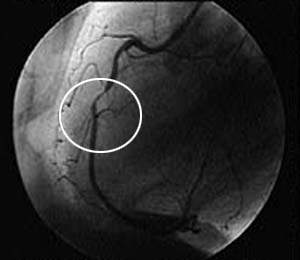

Стеноз коронарной артерии: диагностика и лечение